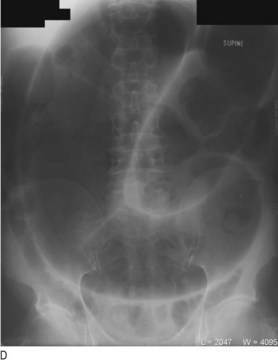

Fig. 8.29 Radiography in gastrointestinal disease.

(A) Air under the diaphragm on chest X-ray due to perforated duodenal ulcer. (B) Dilated small bowel due to acute intestinal obstruction. (C) Dilated large bowel due to toxic megacolon. (D) Dilated loop of large bowel due to sigmoid volvulus.